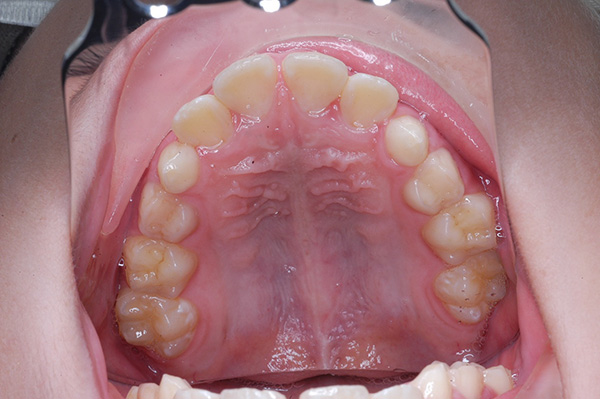

| 口腔内所見 | over jet 5.5mm,over bite 5.0mm,大臼歯関係はⅠ級 、Hellmanのdental ageはⅢBであり上突歯列を呈していた。 |

| パノラマ所見 | 上顎左右側犬歯は近心傾斜し側切歯歯根に重なるように認められた。 |

| 批評・予后 | 埋伏歯の牽引を行い位置異常の改善をした結果、適切な犬歯のガイドが得られ、ほぼ緊密な咬合となったように思う。口元の改善を希望された場合は小臼歯抜歯症例として本格矯正治療を行う予定である。 |